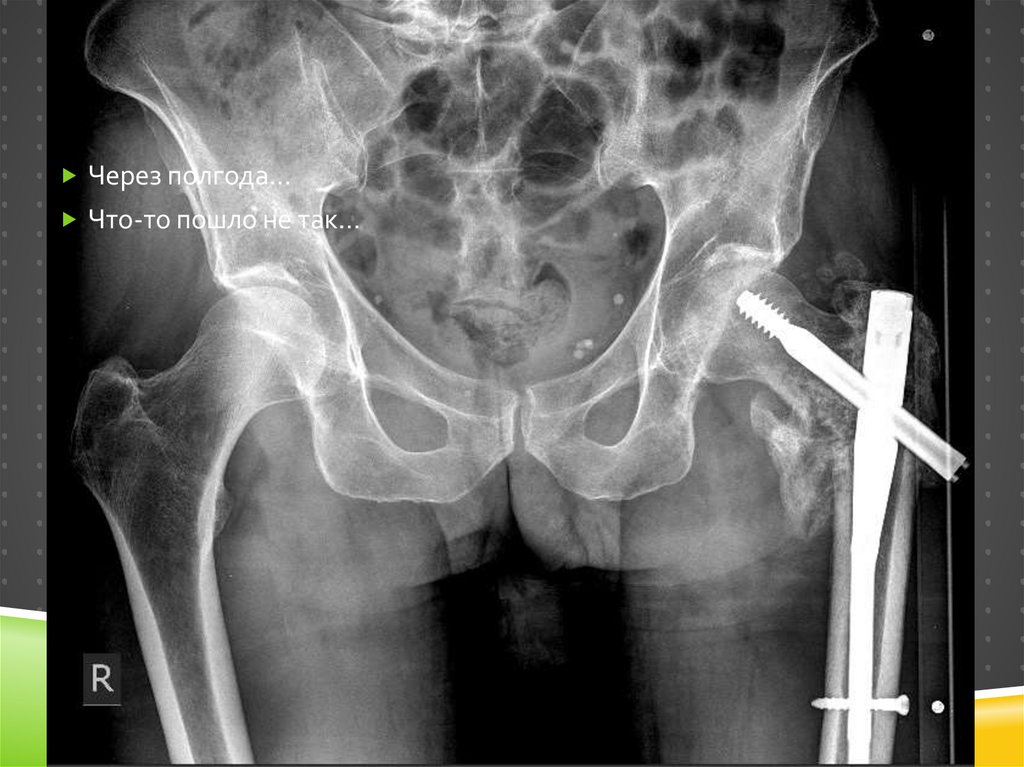

120.

Через полгода…

Что-то пошло не так…